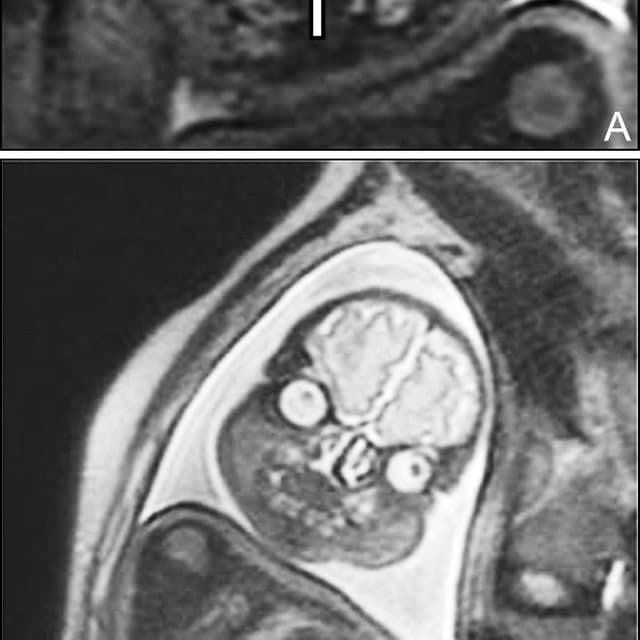

Всегда подмечал в голливудских фильмах такое клише: беременной девушке делают УЗИ, а потом показывают матери и отцу эмбриончик, после чего все начинают умиляться, охать и обниматься, несмотря на то, что на экране по сути ничего не видно. В которой раз можно убедиться в том, что в мелодрамах правды нет. Это подтверждают жуткие МРТ-снимки беременной женщины из реальной жизни. Честно скажу, мне это сегодня приснится. Впечатлительным я бы рекомендовал не смотреть.